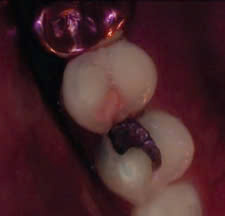

Hình 1: Hình ảnh định lượng ánh sáng huỳnh quang (ánh sáng trắng và ánh sáng huỳnh quang) ở lỗ sâu phía gần bằng thiết bị Qraypen và phim cánh cắn.